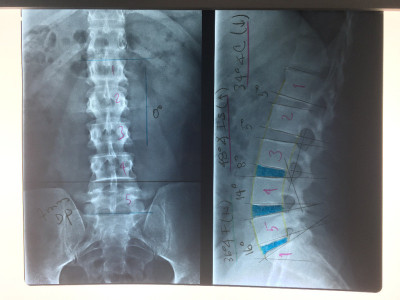

Cirugía de columna de mínima invasión

Envíado por Dr. Hugo Enrique Castro Cordero